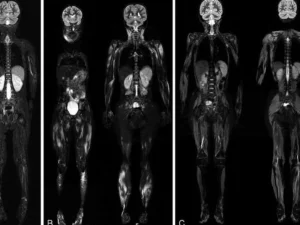

Tüm vücut MR, manyetik rezonans görüntüleme teknolojisi kullanılarak vücudun tamamının ayrıntılı bir şekilde taranmasıdır. Radyasyon içermeyen bu yöntem, manyetik alan ve radyo dalgaları yardımıyla organların ve dokuların yapısını detaylı bir şekilde gösterir. Doktorlar, bu görüntüleri kullanarak hastalıkları teşhis eder ve tedavi planlarını oluşturur.

Tüm vücut MR, genellikle hastalıkların erken teşhisi ve yayılımının değerlendirilmesi amacıyla çekilir. Özellikle kanser taramaları, inflamatuar hastalıklar, enfeksiyonlar ve dejeneratif hastalıkların tespitinde kullanılır. Ayrıca, vücutta mevcut olan anormalliklerin detaylı bir şekilde incelenmesi için de tercih edilir.

Tüm vücut MR, kanser şüphesi olan hastalarda, inflamatuar hastalıklarda, enfeksiyonların yayılımını belirlemek için ve dejeneratif hastalıkların teşhisinde kullanılır. Ayrıca, kronik ağrıların kaynağını tespit etmek, sinir sistemi hastalıklarını ve damar problemlerini değerlendirmek amacıyla da uygulanabilir.

Tüm vücut MR ile kanser türleri, tümörlerin yayılımı, inflamatuar hastalıklar, enfeksiyonlar, dejeneratif hastalıklar, sinir sistemi bozuklukları ve damar hastalıkları teşhis edilebilir. Bu yöntem, özellikle erken teşhis gerektiren hastalıklarda büyük önem taşır ve doktorların doğru tedavi yöntemini belirlemelerine yardımcı olur.